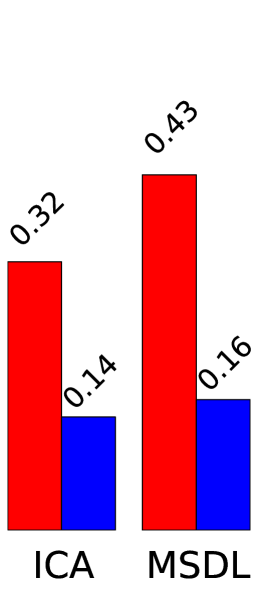

To quantify the usefulness of a set of regions extracted automatically, we consider metrics that characterize two different aspects of the segmentation: the ability to explain newly observed data and the reproducibility of the information extracted, as in the NPAIRS framework [7]. We use Explained Variance (EV) to measure how faithful the extracted regions are to unseen data. Stability with regards to inter-subject variability is measured using Normalized Mutual Information (NMI) over models learned on disjoint subsets of subjects.

Figure 2 presents region extraction results using each method on the same map. In all figures, the threshold applied during region extraction is shown in a given slice to help understanding. Results for each metric are displayed on the right. We vary parameters for each model (smoothing for ICA, 3 parameters of MSDL) and, for each region extraction method, display the best 10% results across parametrization. Figure 4 shows 2 networks out of 42 extracted.

Stability.

Random Walker dominates the stability metric. It uses local maxima to get regions seeds, and will thus split regions even if they are connected after thresholding. Its performance is statistically significant for both dense and sparse atlases and any parametrization. The stability improvement is larger for sparse than for dense maps. This could be due to the inability of random walker to compensate for the original instabilities of the models.

Data fidelity.

Starting from hard thresholding [2], we introduce richer strategies integrating spatial models, to avoid small spurious regions and isolate each salient feature in a dedicated region. Indeed, the notion of regions is hard to express with convex penalties. Relaxations such as total-variation used in [1] only captures it partially, while a non-convex segmentation step easily enforces regions. We find that a Random-Walker based strategy brings substantial increase in stability of the regions extracted, while keeping very good explanatory power on unseen data. Finer results and interpretation may arise by using more adapted metrics, for example a version of DICE that can deal with overlapping fuzzy regions. This point is under investigation.